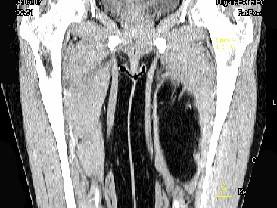

问题 女性,52岁,感左小腿肿胀两年余,活动后稍加重,不痛不热,请结合所提供的图像,选择最佳答案 ( )

选项 A、大腿囊肿 B、大腿脂肪瘤 C、大腿畸胎瘤 D、大腿平滑肌瘤 E、大腿错构瘤

答案 B